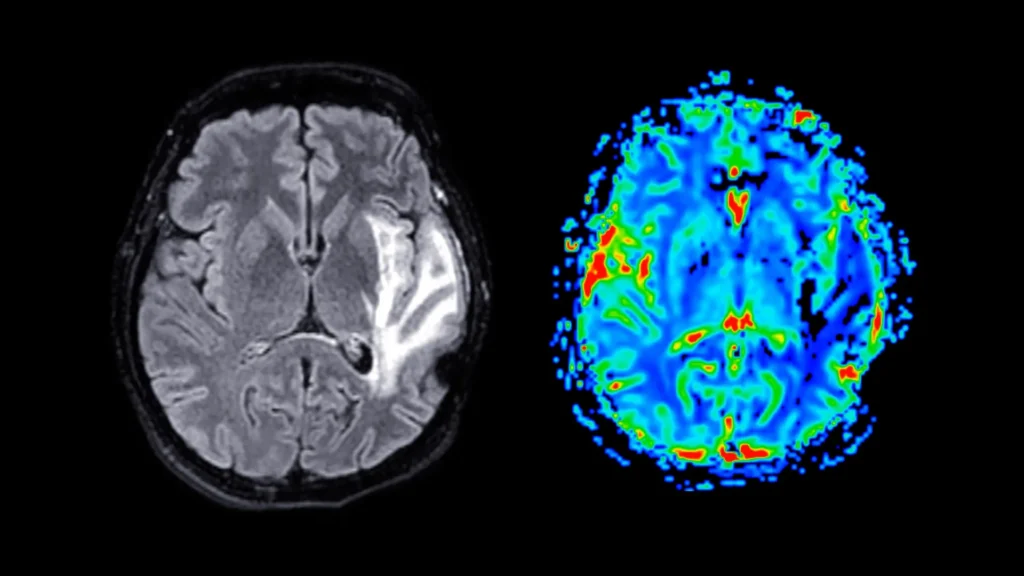

Pesquisas recentes publicadas em The Journal of Clinical Endocrinology & Metabolism sugerem que indivíduos com obesidade e hipertensão arterial podem estar mais propensos a desenvolver demência. A demência é uma crescente preocupação de saúde pública global, e atualmente não existe cura. As pessoas afetadas por essa condição passam por um declínio significativo nas habilidades mentais, […]